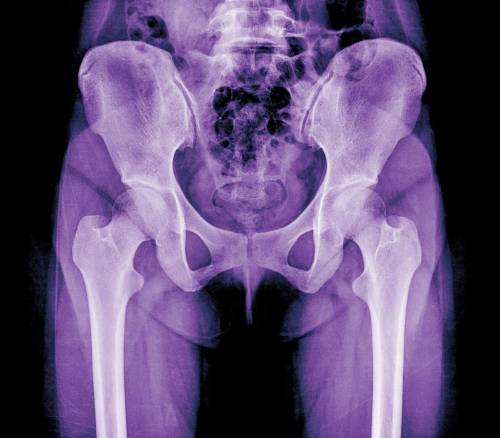

Lo primero que hay que tener en cuenta al hablar de la necesidad o no de una prótesis de cadera, son sus características anatómicas. El traumatólogo Ignacio Ríos Bordón, director de la Unidad de Preservación de la cadera del Hospital Quirónsalud Tenerife, nos explica que se trata de una articulación grande, estable y con mucha movilidad, encargada de soportar y transmitir el peso del tronco a las extremidades inferiores al tiempo que permite al organismo efectuar los movimientos necesarios para mantener la marcha, permanecer de pie, sentarse, etc. Sin embargo, pueden darse ciertas condiciones tanto anatómicas como externas que provoquen lesiones dolorosas o problemas de movilidad que lleguen a desembocar en una artrosis que recomiende implantar una prótesis.

La más frecuente es la rotura del labrum, que es el tejido cartilaginoso que rodea la cadera, similar al menisco de la rodilla, encargado de estabilizar y sellar la articulación. Ciertas disposiciones anatómicas o formaciones óseas anómalas pueden causar el choche entre la cabeza y el cuello del fémur y el acetábulo, que es la cavidad donde encaja, y ocasionar la rotura. Esta lesión es la primera causa de artrosis de cadera y el motivo más frecuente de dolor en el deportista.

En este sentido, el diagnóstico precoz es de vital importancia. Si el choque se trata a tiempo se frena el desgaste de la articulación y se evita la necesidad de implantar una prótesis.